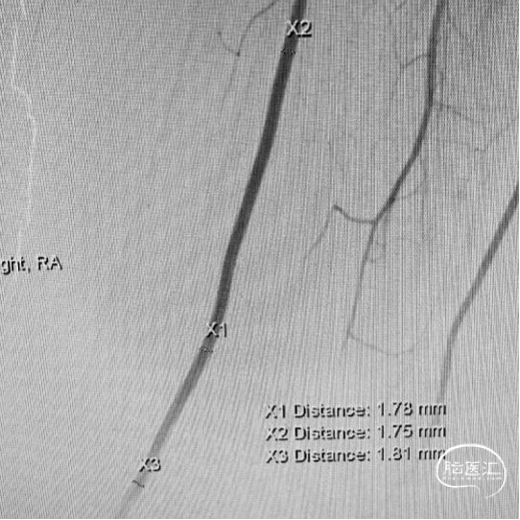

左侧桡动脉造影及超声

患者颞浅动脉、桡动脉较细,需行高流量+低流量搭桥维持大脑中动脉血流。

5. 术中:颈外动脉(ECA)-桡动脉(RA)-大脑中动脉(MCA)M2段搭桥,ICG显示血流通畅。

3.搭桥血流替代后孤立是治疗此类介入复发、血栓化巨大的动脉瘤的终极方式。只有孤立动脉瘤,使瘤体彻底的“去血化”后,结合切开减压,才能预防瘤体增大形成的占位效应。本例术前造影显示先后交通动脉开放代偿较差,故术者选择需高流量搭桥替代颈内动脉血流,保证充足脑血流灌注。下颌下隧道走行桡动脉,可缩短桡动脉所需长度,预防术后压迫。